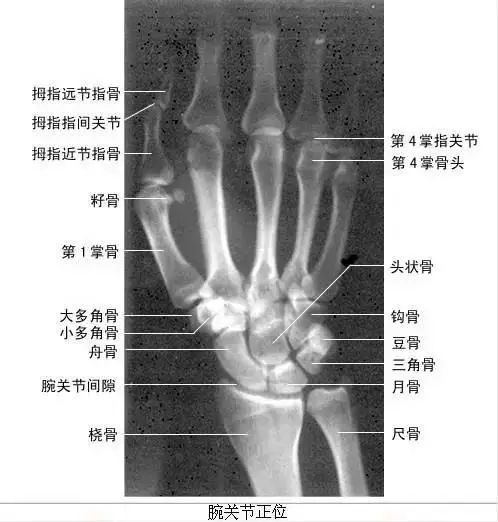

【实用干货】人体体表标志定位与解剖(含人体解剖图)